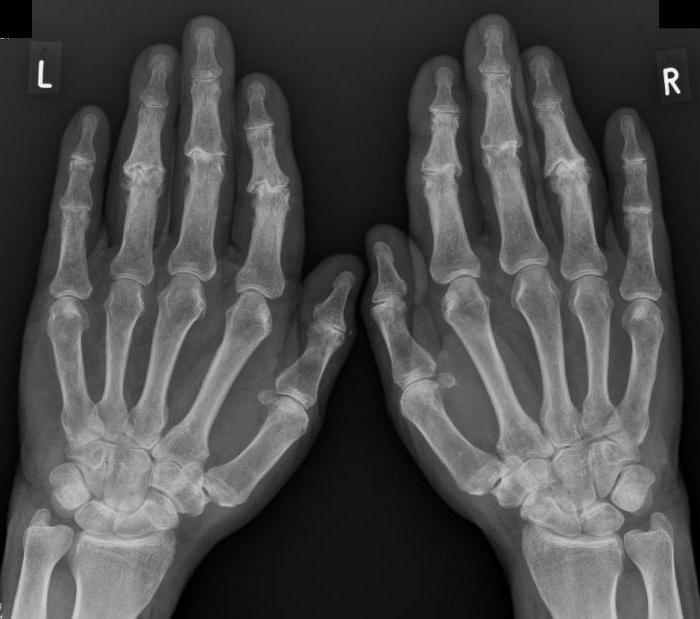

Диагностика неприятных ощущений в ладонях зависит от их причины. Например, при подозрении на ревматоидный артрит врач соберет анамнез, выясняя возможные семейные предрасположенности. Также он назначит анализ крови и рентген суставов. Для диагностики синдрома запястного канала используют электродиагностические методы и физиотерапевтические тесты. Если есть подозрение на остеоартроз, могут быть назначены рентгенография, УЗИ суставов и артроскопия.

Ревматоидный артрит — распространенное заболевание, затрагивающее мелкие суставы пальцев. Боль может быть интенсивной, особенно в области ладони под большим пальцем правой руки. Чаще всего этим заболеванием страдают женщины. Причинами могут быть инфекционные агенты, гормональные изменения и наличие артрита у близких родственников. Симптомы включают:

- боль и дискомфорт в ладонях и пальцах при нажатии;

- ограничение подвижности в пораженных суставах;

- покраснение в центре ладоней;

- отечность;

- деформацию суставов, напоминающую «лебединую шею».